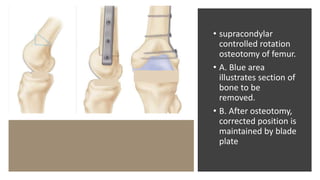

• supracondylar

controlled rotation

osteotomy of femur.

• A. Blue area

illustrates section of

bone to be

removed.

• B. After osteotomy,

corrected position is

maintained by blade

plate